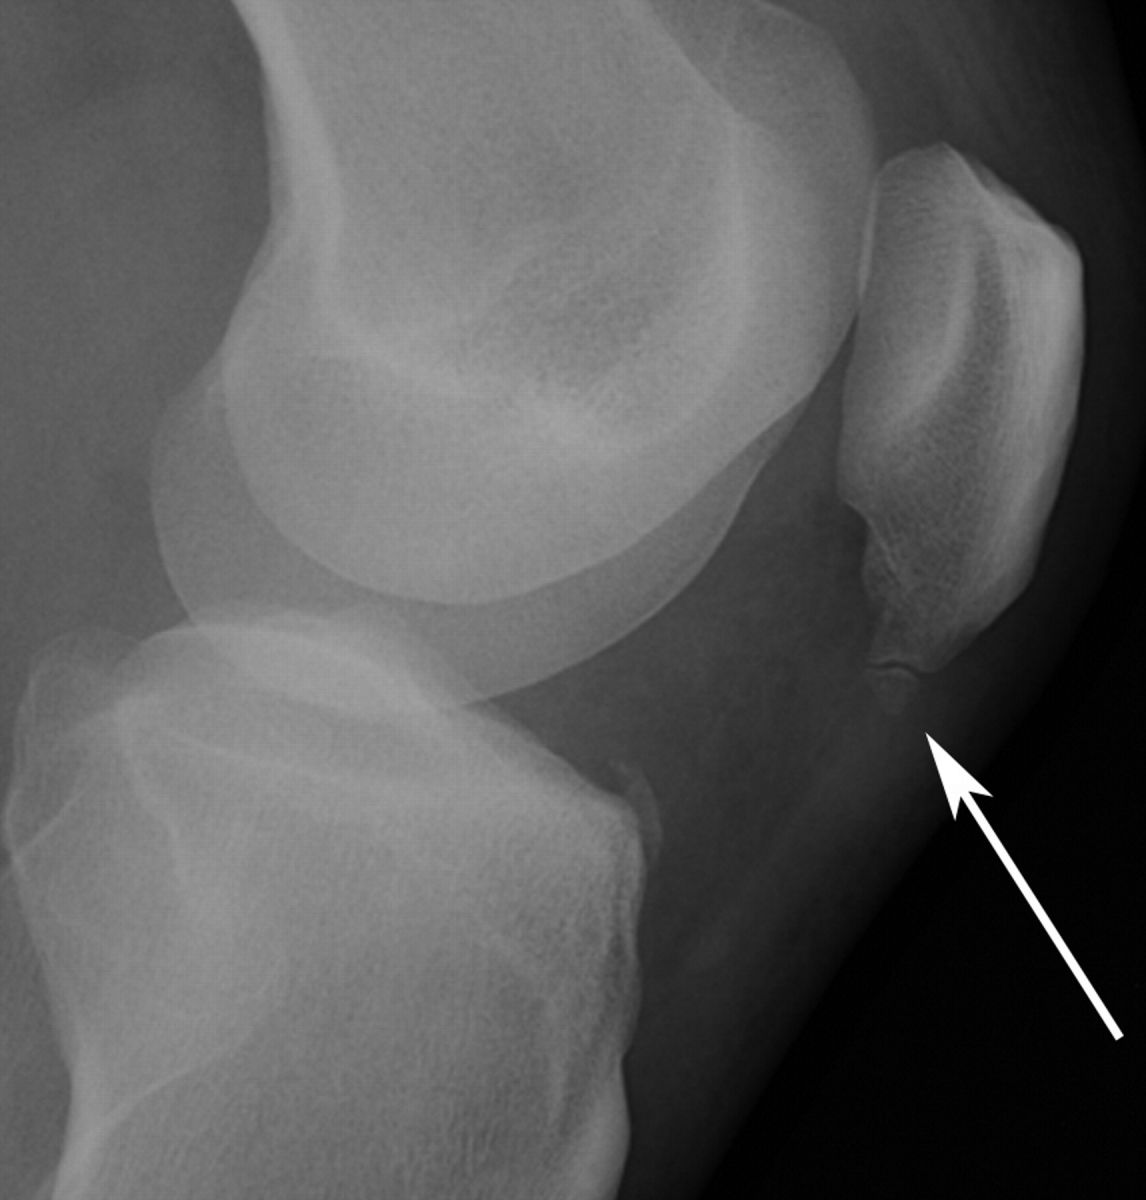

Ларсена йохансона

Ларсена йохансона 146 фото